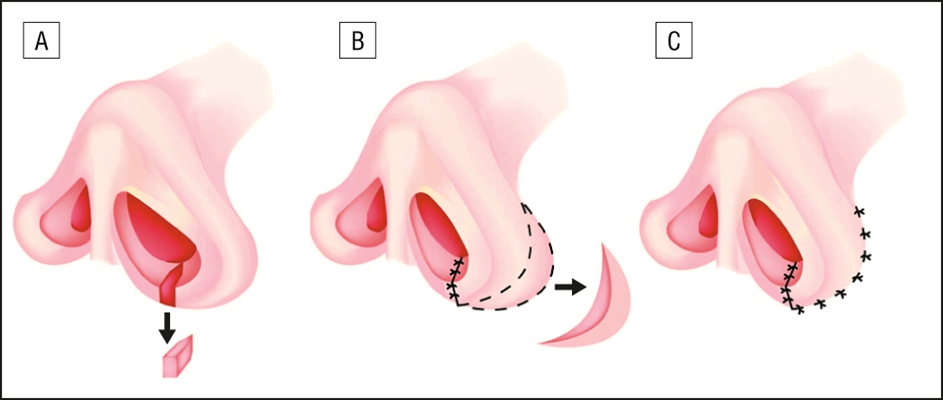

A:做了鼻中隔偏曲矯正手術後,如果沒有明顯的併發症,像鼻中隔的血腫、膿腫、穿孔和遲發性出血,一般是在一週左右就可以恢復,黏膜的傷口也會恢復很好。建議患者避免從事勞累的體力勞動,也少去游泳或者健身。也有少數鼻中隔偏曲矯正手術患者出院了,出現了一些……

A:鼻中隔手術不是特別痛苦,但是術後2-3天由於鼻腔的填塞會有不適。鼻中隔手術術中可以通過全麻進行手術,全麻下沒有感覺,所以術中並沒有特別痛苦。術後由於鼻中隔要填塞填充物進行止血,防止血腫,一般可以用膨脹海綿或者凡士林紗條。早期通常用凡士林紗條……

A:鼻中隔偏曲手術後已經一個月了,可以恢復正常的運動鍛鍊,即使是大量的運動也不會影響鼻中隔偏曲的手術效果。建議在恢復相應的體育鍛煉的過程中,一定要注意保護好鼻子,因為畢竟鼻子才剛剛做過手術,內部的結構穩定性才剛剛恢復,對於外部的暴力撞擊仍然沒有……